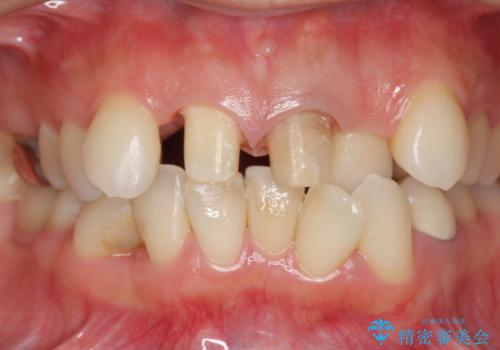

著しいがたつきによる清掃困難 歯牙抜去とセラミック治療

- 前歯の変色の改善を希望され来院されました。

X線写真より、充填剤の突き出た状態の根管治療の再治療を行い、セラミック治療を計画すると同時に、

歯ブラシがしづらく虫歯の原因となっている歯の位置の悪い右上側切歯の抜去を行います。

清掃を難しくしている歯を抜去することで虫歯の再発を防ぐような治療方針としました。